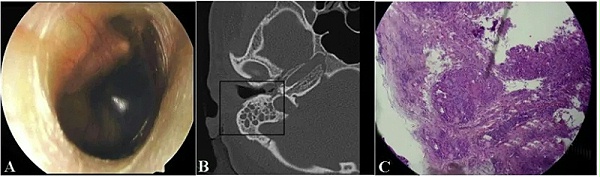

640.webp (2)

图6  以鼓室积液为首发表现的结核性中耳炎。耳纤维内镜检查显示中耳积液,鼓膜完整(A)。颞骨CT扫描显示乳突气房积液,中耳软组织影,无明显骨破坏(B)。组织学检查发现许多多核巨细胞和肉芽肿伴干酪样坏死组织(C),考虑结核性中耳炎。(引自 Phan Huu Ngoc Minh  Otolaryngology Case Reports,2020